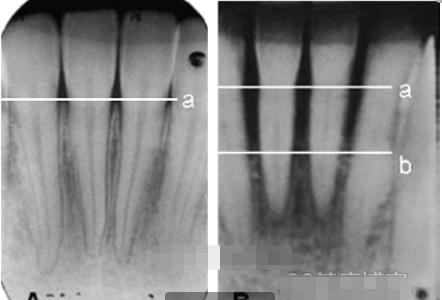

- 水平吸收就是牙槽骨的整体高度发生下降,每一个牙根在牙槽骨中的部分都有减少。

- 垂直吸收就是牙槽骨发生斜向或者垂直方向的吸收,高度降低不多但是牙根部位会有比较明显的吸收现象。